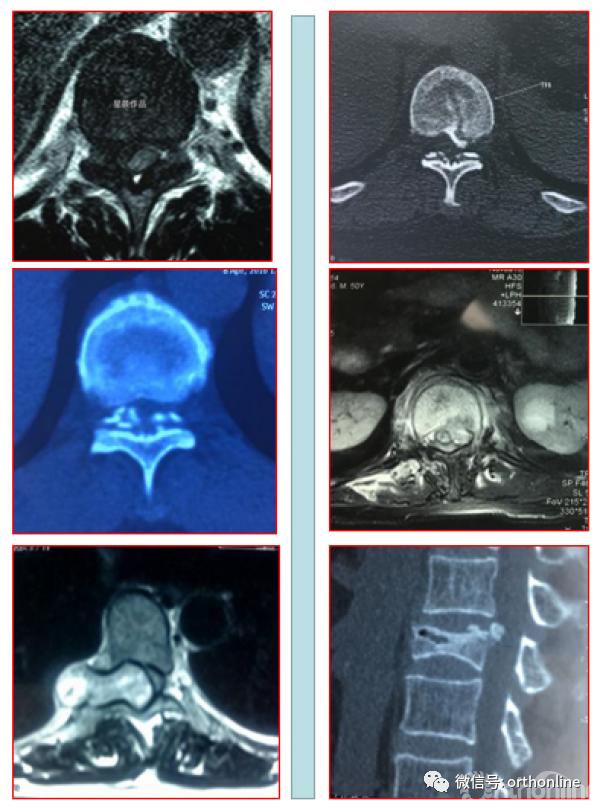

二、后纵韧带骨化形态学分型

1.按照矢状位CT分为线型、鸟嘴型、连续波形、连续圆柱形和混合型。

OPLL的CT矢状位分型为A.线性(Linear type);B.鸟嘴型(Beak type);C.连续波形(Continuous waveform type);D.连续圆柱形(Continuous cylindrical type)。混合型(Mixed type)为同时具有A-D两种及以上类型